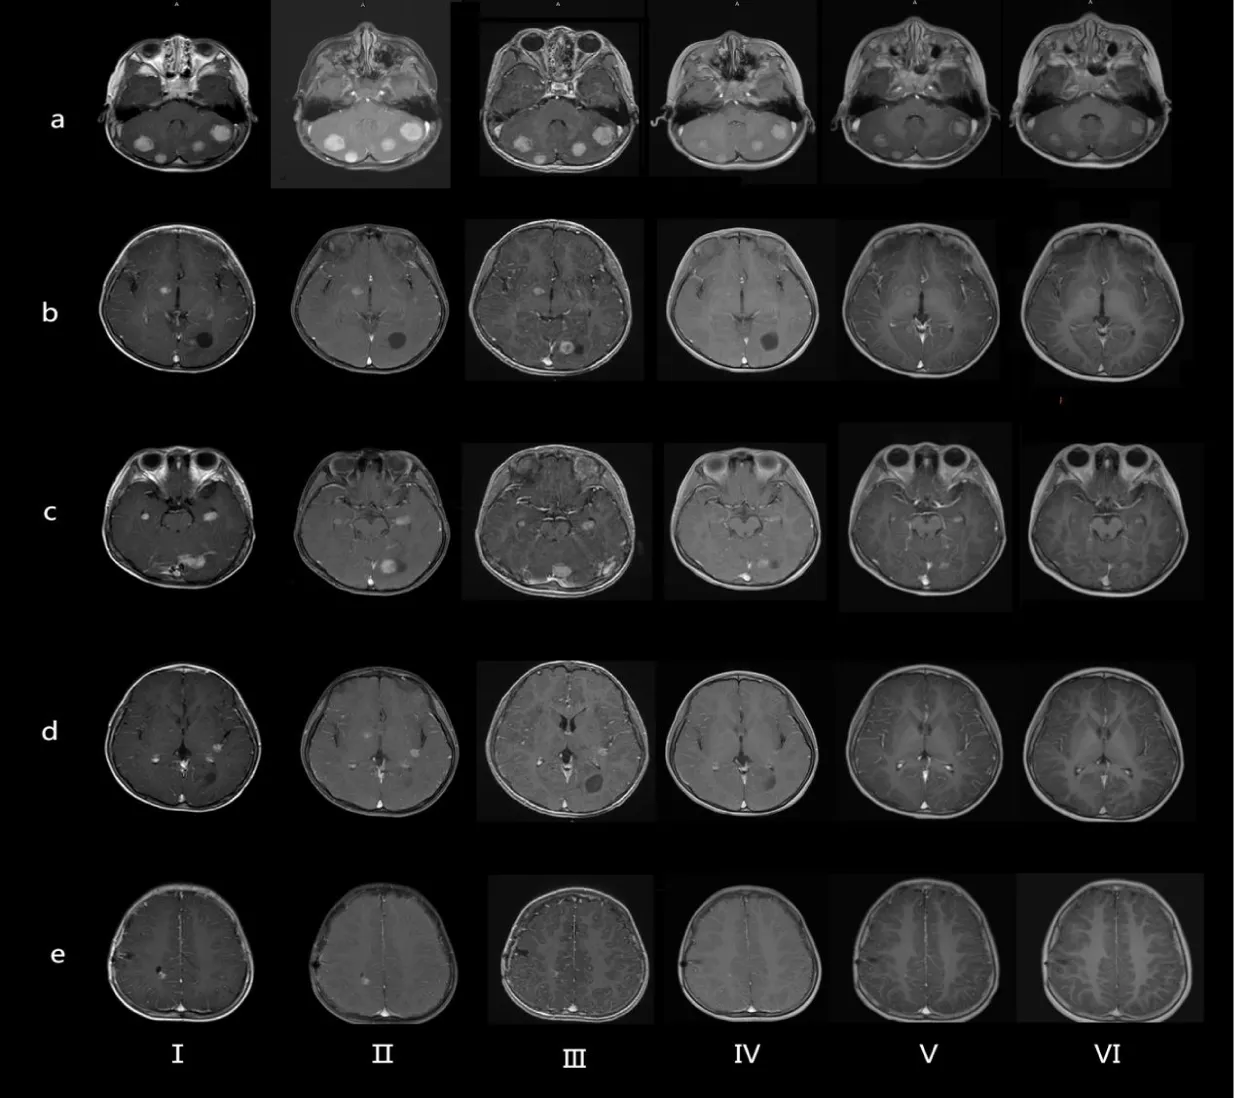

A previously healthy 4-year-old boy presented with a 2-year history of progressive left eye esotropia, without accompanying systemic symptoms such as headache, fever, or vomiting. His medical and family histories were unremarkable, with no exposure to contaminated water, undercooked meat, or pigeon feces. Neurological examination revealed subtle signs: slight limitation in left eye abduction and a positive Babinski sign on the left side. Initial laboratory tests showed normal hematologic parameters (WBC 7.76×10⁹/L, hemoglobin 130 g/L) and mildly elevated serum alkaline phosphatase (273 U/L) and calcium (2.31 mmol/L). Brain MRI demonstrated multiple heterogeneous lesions in bilateral cerebellar hemispheres, left occipital lobe, medial temporal lobes, right thalamus, and right frontal/parietal lobes. These lesions exhibited ring enhancement with perilesional edema and some with adjacent cystic components (Figures 1a-e).

Lumbar puncture under general anesthesia showed elevated CSF pressure (>330 mm H2O), lymphocytic pleocytosis (7×10⁶/L, 89% lymphocytes), and elevated protein (634 mg/L), though glucose levels were normal (2.7 mmol/L). Next-Generation Sequencing (NGS) of CSF identified Entamoeba dispar (447 reads), while extensive serological tests for bacterial, fungal, and parasitic pathogens (including tuberculosis, toxoplasmosis, and neurocysticercosis) were negative. Chest CT revealed subpleural and mid-lung field nodules (Figure 4), suggesting possible pulmonary involvement. The patient received three 10-day courses of metronidazole (50 mg/kg/day) over five months, with intervals of 1-2 months between courses. Follow-up MRI of 4 years showed progressive resolution of brain lesions, including absorption of the cysts, reduction of lesion size, decreased enhancement and alleviation of the perilesional edema (Figures 5a-e).